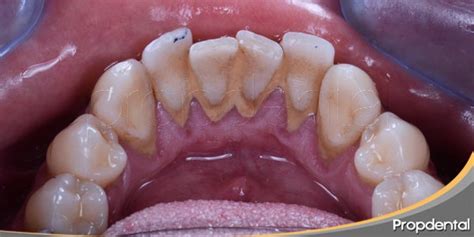

El sarro o cálculo dental es un agregado de bacterias, minerales y restos de comida que se deposita sobre los dientes. Se parece a los depósitos de cal que se acumulan en nuestras cocinas y baños. El residuo depositado sobre los dientes inflama las encías y provoca gingivitis y periodontitis.

El sarro dental es una capa de suciedad y residuos calcificados que se acumula en los dientes como consecuencia de una higiene oral insuficiente o ineficiente. Esta capa de suciedad también se puede amontonar en el borde o debajo de las encías, llegando a irritar los tejidos gingivales.

El sarro está colonizado por las bacterias de la cavidad oral o placa bacteriana, responsable a su vez de muchas de las patologías de los dientes y encías. El sarro en los dientes se forma por la acumulación progresiva de residuos de alimentos, proteínas salivares y restos microbianos, que se calcifican alrededor de las superficies de los dientes como consecuencia de la precipitación de las sales minerales y los iones presentes en la saliva.

El sarro se forma cuando la placa que no se ha eliminado con el cepillado y el uso de hilo dental se mineraliza con los minerales presentes en la saliva. La placa puede comenzar a endurecerse y convertirse en sarro en tan solo 24 a 72 horas después de la formación de la placa.

Aunque las acumulaciones de sarro suelen producirse por una higiene oral deficiente, una vez formadas no pueden eliminarse con el cepillado corriente ni ningún otro tratamiento que el paciente pueda practicar en su casa. No obstante, si no nos cepillamos de forma correcta, la placa no tardará en acumularse y formar sarro.